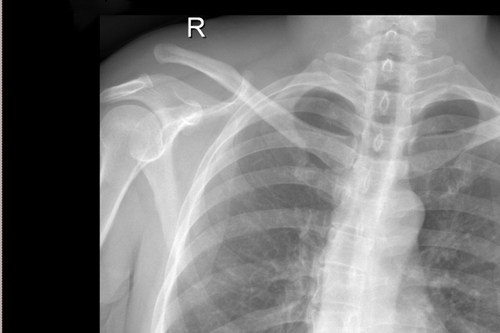

传统手术术后DR

骨三科主任朱述浪表示,近年来,随着生活水平的提高,患者对手术方式、手术效果的心理预期也不断提高。传统手术通过使用锁骨钩钢板来治疗肩锁关节脱位,其固定方式虽牢靠,但手术切口较大,术后极易出现脱钩、肩峰撞击,下骨溶解甚至造成骨折,疼痛发生率非常高,同时,内固定需2次手术拆除,且拆除后存在再脱位的可能。相比之下,带袢钢板内固定术能够有效恢复肩锁关节各方向的稳定性,不但符合肩锁关节生物学特性,还能最大程度地减少患者的创伤,并尽可能达到美容效果。该手术的开展,有望为广大患者提供更安全、更人性化的医疗服务。